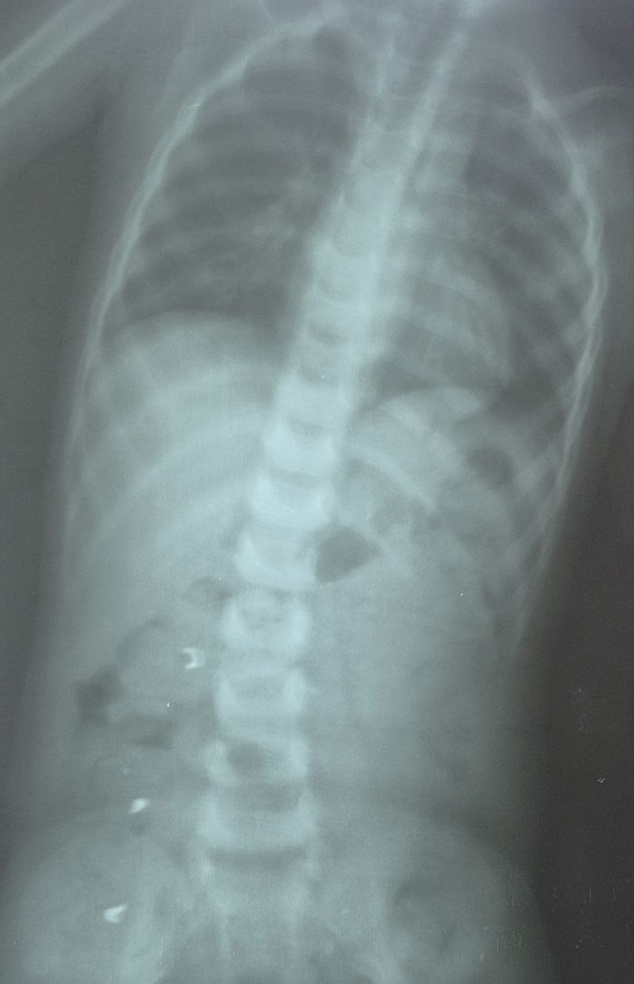

В Хвалынской больнице был сделан рентгеновский снимок - инородное тело находилось в желудке. Малыша перенаправили в Балаково. Контрольный снимок показал, что инородное тело состоит из трех частей и находятся они уже не в желудке, а распределились по кишечнику.

"Ребенок вместе с мамой госпитализирован. Он находится под наблюдением врачей. Прогноз благоприятный. Однако, до выхода частей цепочки естественным путем, малыш будет оставаться в стационаре", - рассказали в Балаковской клинической больнице.